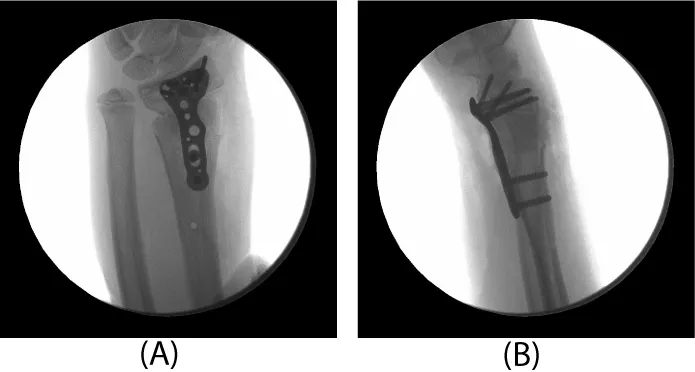

The patient remained immobilized in a short arm cast until 5 weeks post-operatively. At that time, he was taken back to the operating room for Kirschner wire removal. A post-operative splint was placed for one additional week. At that time, radiographs revealed complete healing of the fracture in adequate position and therapy was initiated. At twelve weeks post-operatively, the patient was noted to have full wrist mobility and he was allowed to progress with activity as tolerated. Radiographs revealed complete healing of the fracture and the physis appeared un-affected (Figure 3).

The patient returned two years later due to ulnar sided wrist pain. Clinical examination showed an obvious deformity with a prominent ulna and radial translation of the hand relative to the forearm axis. Radiographs revealed a partial distal radius physeal closure on the radial aspect where the original pins had been positioned. There was a reversal of the normal radial inclination on the frontal film and significant ulnar positive variance (Figure 4). The physis of the distal ulna remained open.